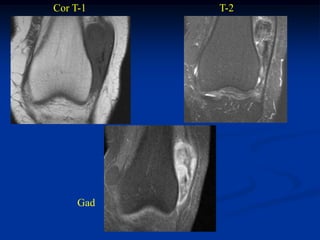

Case #1197

CLASSIC

37 year female with

hibernoma triceps m

Sagittal T-1 MRI

Axial T-1 MRI

Axial T-2 MRI

Axial gad

contrast MRI

Sagittal gad contrast